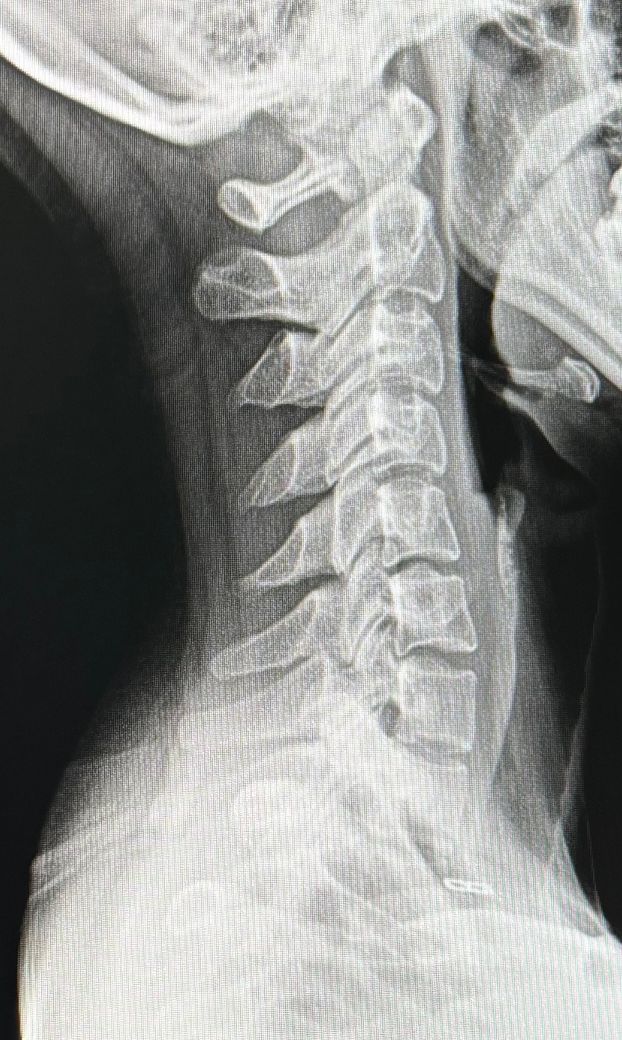

일자목인가요?? 상태가 많이 심각한가요

병원에서 엑스레이 찍었는데 일자목이라 하셨습니다 제가 보기에는 중간에 커브도 살짝 보이는것같은데 일자목인가요 거북목인가요?

일자목인데, 엑스레이상에서만 보았을때 일자목으로는 어느정도 심각한 형태로 보입니다.

커브가 부족한 편이며, 상부-중부 경추 사이가 일직선을 곧아져 있습니다. 보통은 일자목으로 부릅니닫.

엑스레이를 보았을 때 목뼈의 C커브가 제대로 형성되지 않고 일자로 되어있어 일자목으로 진단 할 수 있습니다.

• 엑스레이 사진 한 장만 가지고 정확히 어떻다 이야기 하는 어렵습니다만, 커브가 일반적인 수준에 비해서 없다시피 할 정도로 보이며 일자목 상태로 볼 수 있는 엑스레이 소견이 맞습니다.

이정도면 일자목에 가까운 상태입니다. 경추부 하부는 커브가 있지만 위로 갈수록 일자형태를 만들고 있으니 일자목 이라고 하는것입니다. 거북목은 거북이가 목을 쭉 빼는 자세를 닮았다고 하여 붙은 말이고 서로 동일한 질환으로 통용됩니다. 등이굽거나 턱을 쭉 빼는 자세를 피하시고 곧고 바른자세를 유지하시기 바랍니다.

우리의 인체는 목의 커브 같은 경우 C자 커브의 모양을 갖지만 지금 같은 경우는 일자목으로 보입니다.

아마 중간에 보이시는 커브는 역 C자로 가는 단계로 판단이 되지만 엑스레이는 옆, 사선, 정면 등 여러 촬영본을 통합해야하며 엑스레이로만 판단하기엔 어렵기에 너무 걱정하지 않으셔도 괜찮습니다.